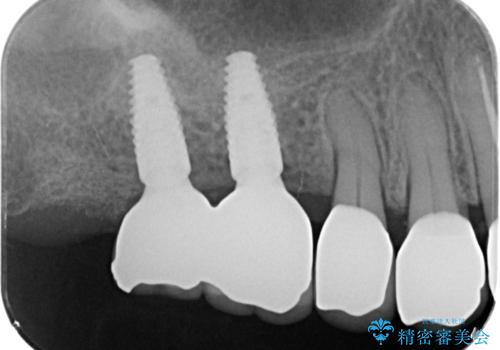

外から見てもなかなかわかりませんが、左側奥歯に大きな虫歯がX線写真で認められるので矯正治療前に虫歯治療を行っていきます。

見るだけでは歯の変色なのか、虫歯なのか判断がつきにくい場合X 線写真による検査は最も信頼度が高いといえます。

今回矯正治療に先んじて行われたX 線写真検査により大きな虫歯が見つかり、先に処置を行うことができました。